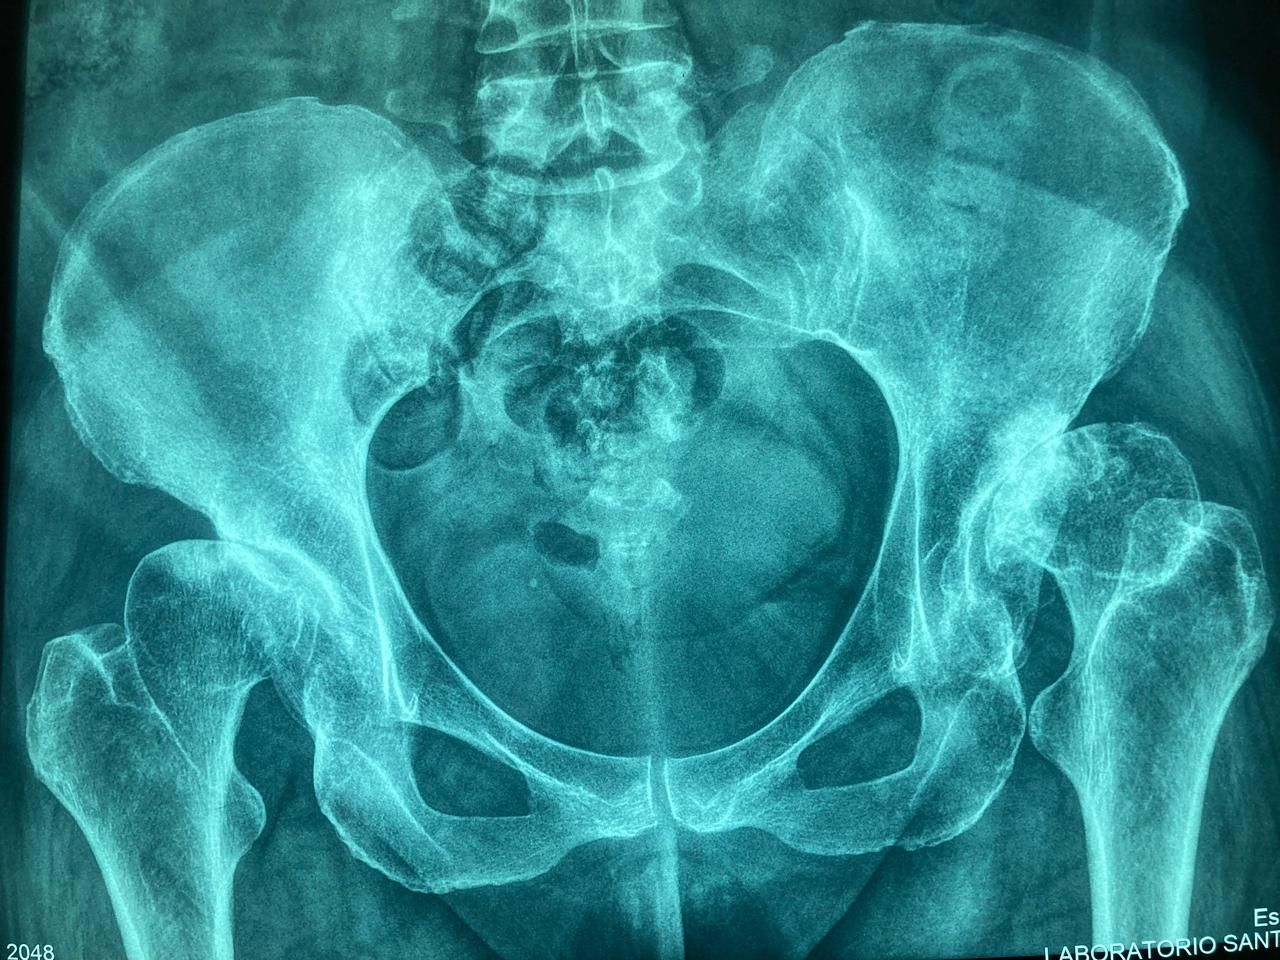

La ortopedia se enfoca en las enfermedades y alteraciones del sistema músculo-esquelético, tanto en adultos como en pacientes jóvenes. El Dr. Juan Carlos Torres Archila, especialista en ortopedia en Comitán, Chiapas, ofrece atención integral y personalizada para afecciones crónicas, degenerativas o congénitas que afectan huesos, articulaciones, músculos, tendones y ligamentos.

Cada caso es valorado a profundidad para proponer tratamientos conservadores (rehabilitación, ejercicios, ortesis) o procedimientos quirúrgicos cuando son necesarios, como artroplastías (colocación de prótesis articulares) o cirugías mínimamente invasivas como la artroscopía.